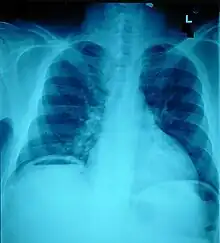

Ten percent of people with polytrauma who had no signs of abdominal injury did have evidence of such injuries using radiological imaging.[1] Diagnostic techniques used include CT scanning, ultrasound,[1] and X-ray.[7] X-ray can help determine the path of a penetrating object and locate any foreign matter left in the wound, but may not be helpful in blunt trauma.[7] Diagnostic laparoscopy or exploratory laparotomy may also be performed if other diagnostic methods do not yield conclusive results.[5]

Ultrasound

Ultrasound can detect fluid such as blood or gastrointestinal contents in the abdominal cavity,[1] and it is a noninvasive procedure and relatively safe.[4] CT scanning is the preferred technique for people who are not at immediate risk of shock, but since ultrasound can be performed right in an emergency room, the latter is recommended for people who are not stable enough to move to CT scanning.[1] A normal ultrasound does not rule out all injuries.[14]

CT

People with abdominal trauma frequently need CT scans for other trauma (for example, head or chest CT); in these cases abdominal CT can be performed at the same time without wasting time in patient care.[4]

CT is able to detect 76% of hollow viscous injuries so people who have negative scans are often observed and rechecked if they deteriorate.[15] However, CT has been demonstrated to be useful in screening people with certain forms of abdominal trauma in order to avoid unnecessary laparotomies, which can significantly increase the cost and length of hospitalizations.[16] A meta-analysis of CT use in penetrating abdominal traumas demonstrated sensitivity, specificity and accuracy >= 95%, with a PPV of 85% and an NPV of 98%.[17] This suggests that CT is excellent for avoiding unnecessary laparotomies but must be augmented by other clinical criteria to determine the need for surgical exploration (23.37 positive likelihood ratio, 0.05 negative likelihood ratio).